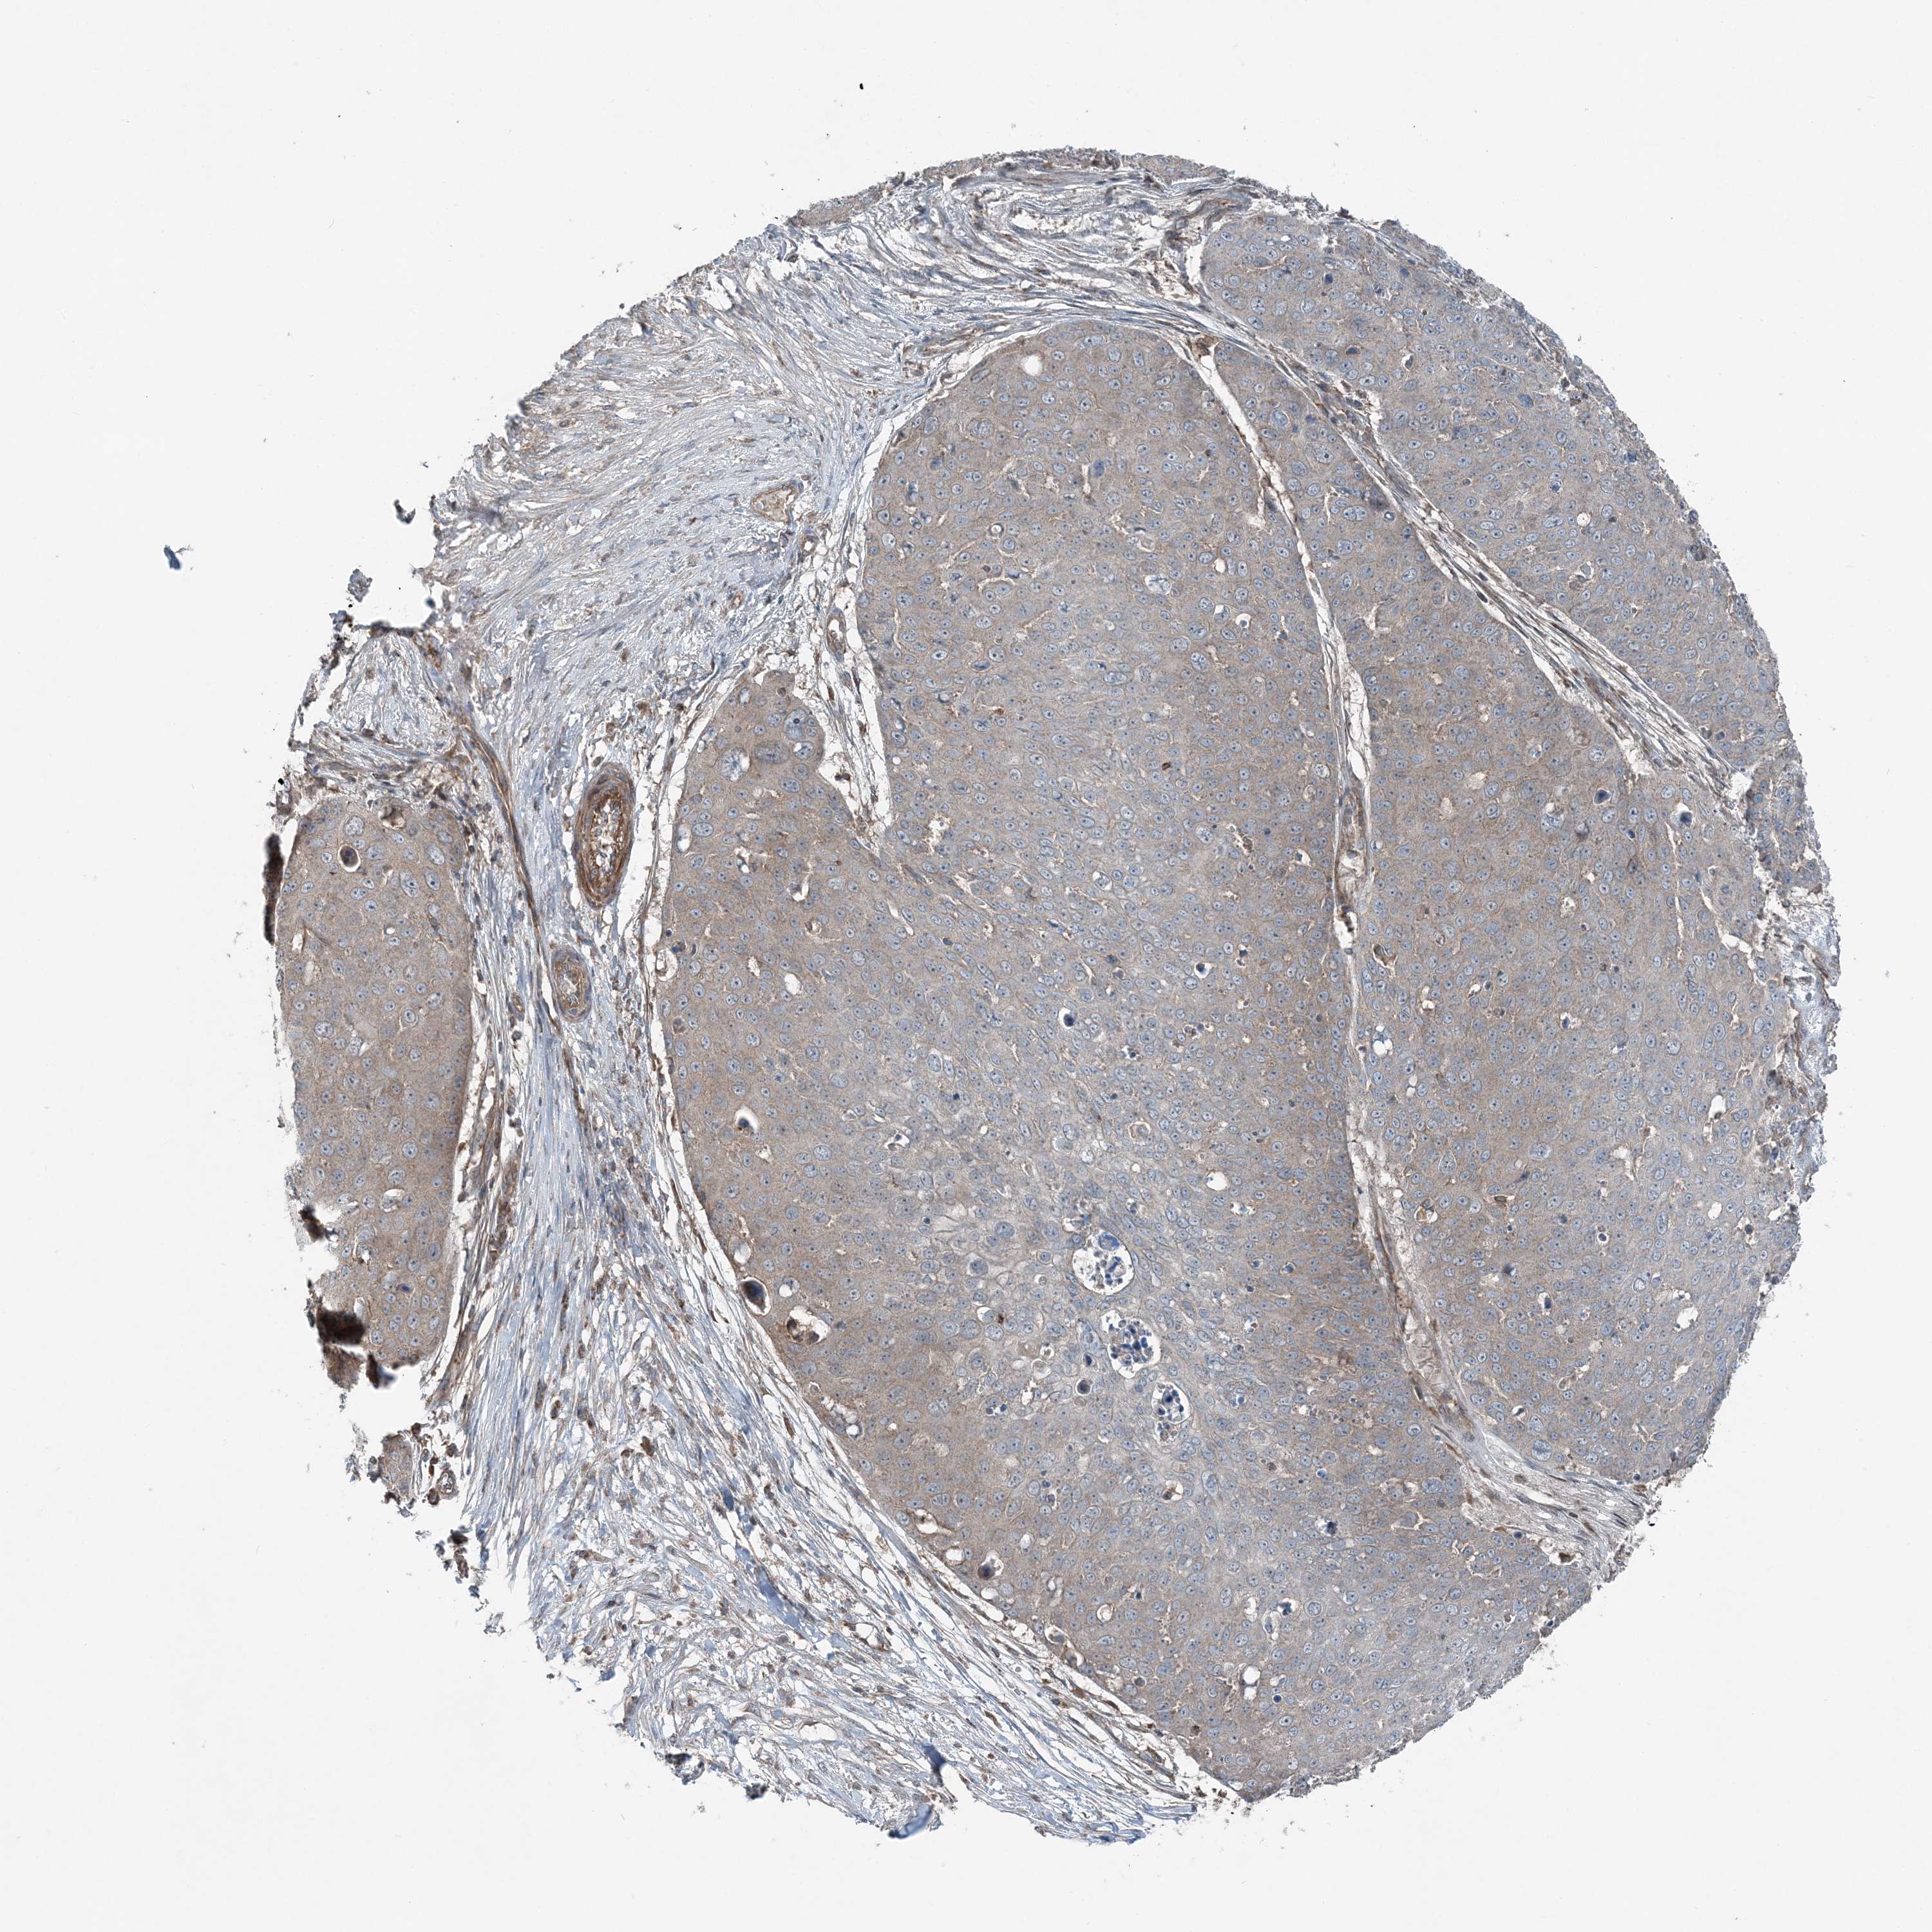

SKIN CANCER - Protein expressioni

A mouse-over function shows sample information and annotation data. Click on an image to view it in a full screen mode. Samples can be filtered based on level of antibody staining by selecting one or several of the following categories: high, medium, low and not detected. The assay and annotation is described here.

Antibody stainingi

Antibody staining in the annotated cell types in the current human tissue is reported as not detected, low, medium, or high, based on conventional immunohistochemistry profiling in selected tissues. This score is based on the combination of the staining intensity and fraction of stained cells.

Each image is clickable and will lead to virtual microscopy that enables deeper exploration of all samples and also displays staining intensity scores, fraction scores and subcellular localization as well as patient and tissue information for each sample.

Antibody HPA036492

Basal cell carcinoma